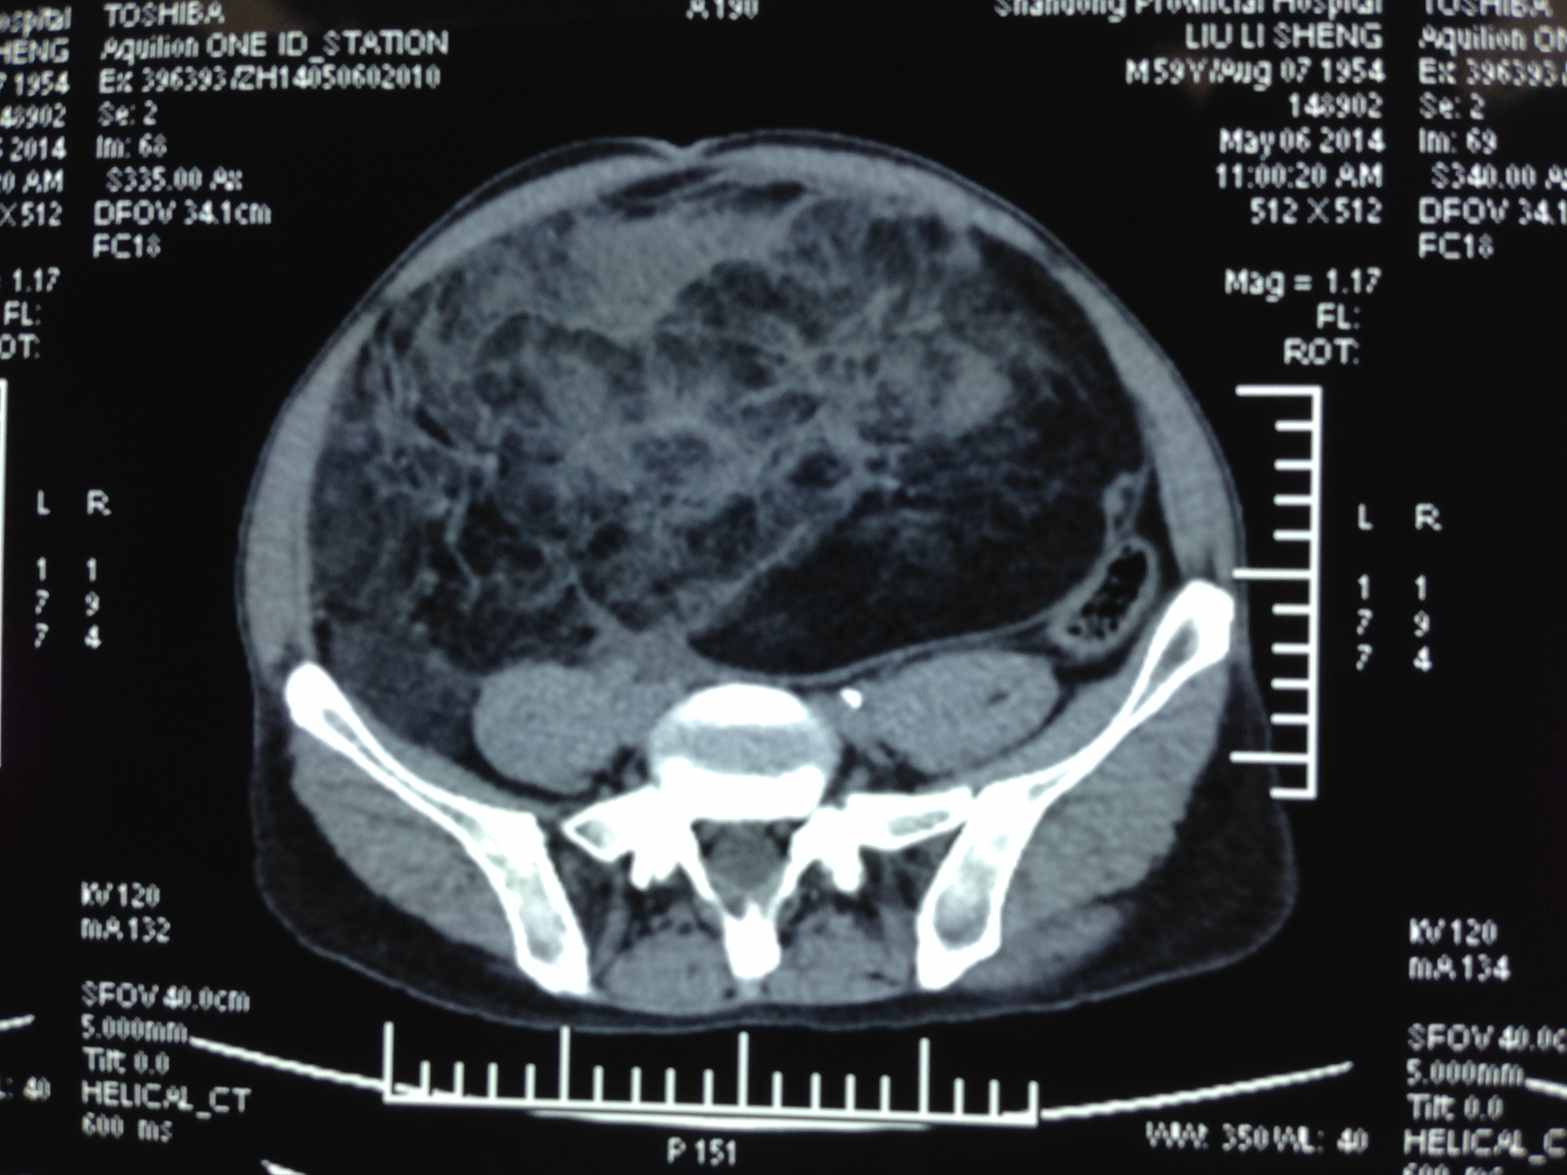

5月6日,抱着一线希望,患者就诊于我院东院区肝胆外科。该患者住院后,立即引起了全科的高度重视,主管医生对患者进行了详细的全面检查。通过对患者CT检查结果分析,初步判断为临床上极为罕见的腹膜后巨大脂肪肉瘤 。在科室主任卢俊教授的组织下,常宏主任医师、周旭副主任医师、李洪光副主任医师、刘方峰主治医师、朱化强主治医师等全体医生对患者的病情进行了认真讨论,仔细分析,最终认为手术切除是目前最有效的治疗方法,并制订了详尽的手术计划。

5月13日,在手术室、麻醉科的协助配合下,由卢俊主任医师主刀,在助手周旭副主任医师,朱化强主治医师的配合下,开始实施手术。术中发现巨大的肿瘤起源于腹膜后,向前挤压侵占了腹腔大部分空间,向上达肝下缘,向下延伸到盆腔,将右侧输尿管推挤到脊柱左侧,而将回盲部及阑尾推挤至脐上方偏左。严重的解剖结构改变使得手术难度和风险都远远超出了术前的预测。但卢俊主任沉着应对,凭借多年丰富的手术经验和高超的手术技巧,小心仔细地分离,保护好重要的血管及输尿管,经过3小时的努力,终于将该巨大肿瘤完整切除,切除后的肿瘤重达10公斤,整个手术过程出血量不足100ml。经术后病理分析确诊为高分化脂肪肉瘤。